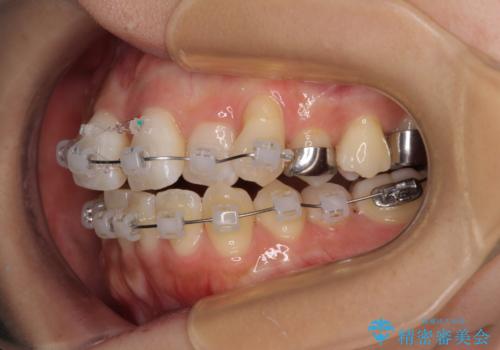

- クリアブラケット

- 1年3ヶ月

- 上下前歯のデコボコを気にして来院された患者様です。

上顎歯列が下顎の歯列に対して狭小であり、一部下顎の奥歯が上顎よりも外側に位置している状態でした。

上顎の急速拡大装置を使用して上顎骨を側方に拡大することで上顎歯列を拡大し、下顎歯列も拡大できるようにすることで、歯列を整えることとしました。